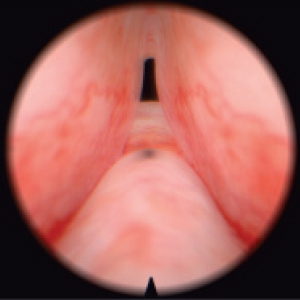

Diagnostic and surgical skills in Hysteroscopy & TUR

Resectoscope for hysteroscopy

Real resectoscope handle. Pedals for coagulation and electric dissection.